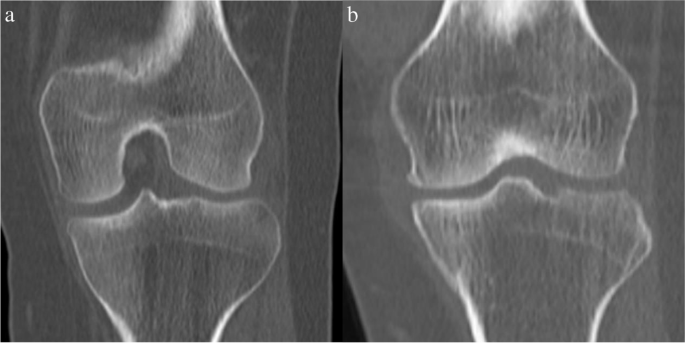

- MRI: To examine soft tissue damage, including ligaments and cartilage.

- X-rays: To identify changes in bone structure and joint space narrowing.

Diagnosing Knee Arthritis

The diagnostic process generally involves the following steps: